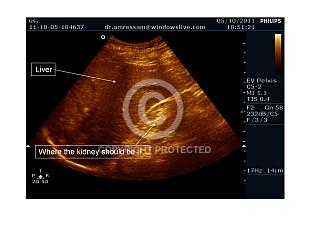

Hepatorenal angle

Miscellaneous views

Pregnancy after renal transplant